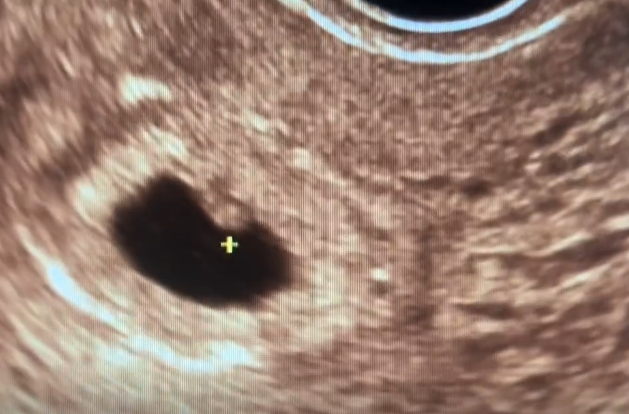

看完结果,说无胎心胎芽,连卵黄囊都没有,我整个人都在发抖,却无能为力,完全接受不了。本以为不用再早起摸黑去医院排队,能数着日子盼预产期了。五周末开始有孕反,干呕、腹部有拉扯感,我还以为是宝宝在长大呢。